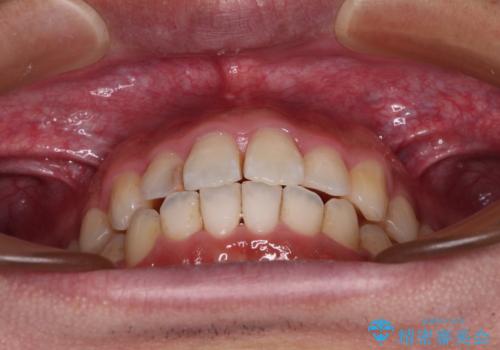

前歯のデコボコと突出感をマウスピース矯正できれいに

- 上下前歯のデコボコと突出感を気にして来院された患者様です。

目立たない装置を希望されたため、インビザラインによるマウスピース矯正を行うこととしました。

矯正治療後に銀歯をセラミックに替えたいとの要望があり、概ね歯列が整ったところで銀歯をセラミックに替え、仕上げにインビザライン1セットを使用して最終的に歯列を整えました。